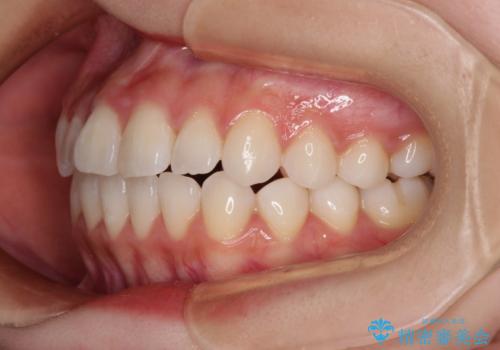

- 前歯のデコボコと非接触の上下前歯を気にして来院された患者様です。

上下前歯の隙間は舌の突出癖によるもので、隙間改善のためには舌のトレーニングがとても重要となります。

口元の突出感はないため、抜歯矯正の適用ではありませんが、デコボコを解消する際に外側に拡大されてしまうと治療前と比べて出っ歯になった印象にもなるため、舌の突出癖の改善が必須となります。

治療開始当初は舌の突出癖が改善されておらず、上下前歯の隙間がより顕著な状態となりました。

舌のトレーニングは、突出癖がなくなるまで必要であり、矯正治療後に突出癖が残ると、あっという間に隙間が空き、後戻りでデコボコとなってしまいます。